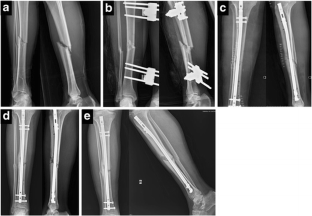

Fig. 1